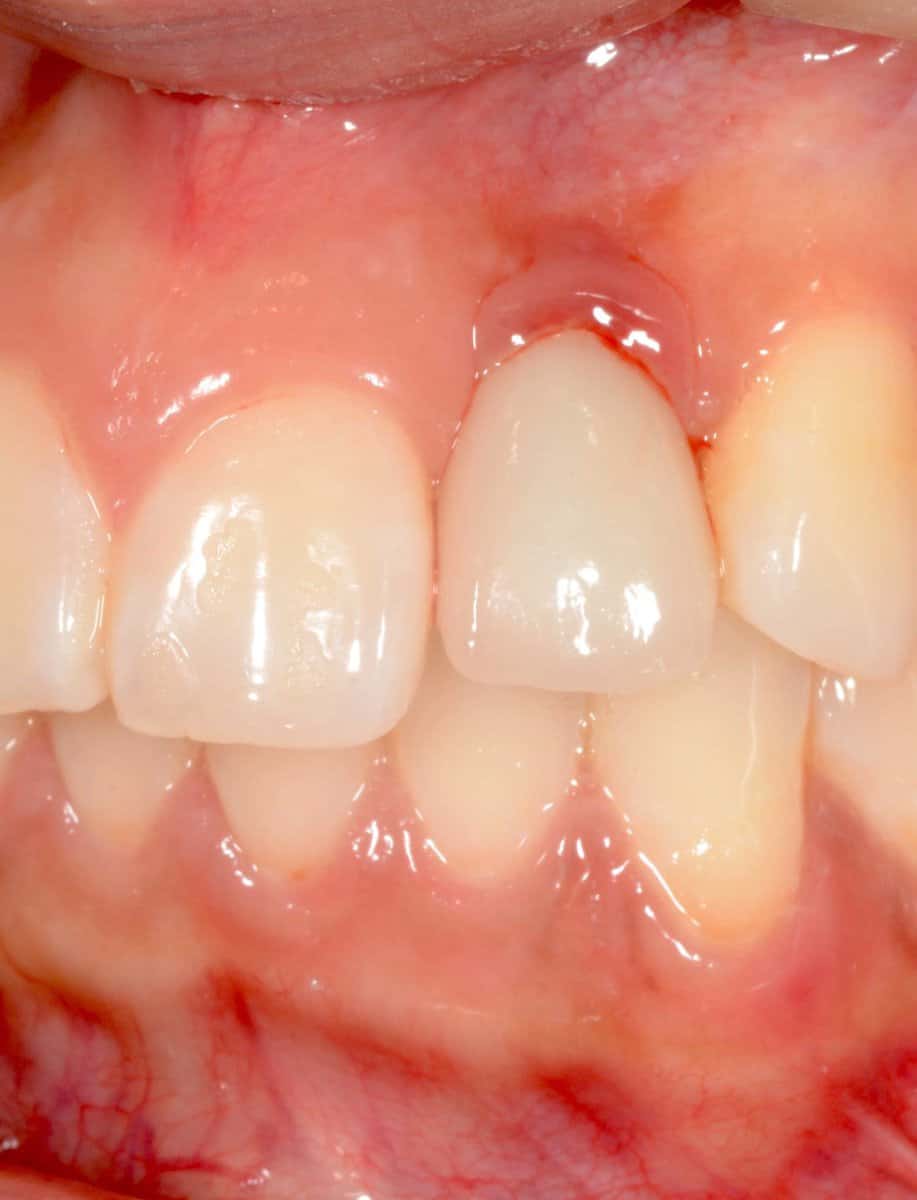

Locator abutments of mandibular overdenture, burried under the swollen and inflamed oral mucosa. Resolution of the inflammation in such cases is very challenging, but unless some surgical adjustment of the peri-implant tissues takes place the problem can be recurrent.

Baloon-style swelling of the tissues around locator abutment of mandibular overdenture, combined with Peri-implantitis. Adjustment of the soft tissues in combination with teh peri-implantitis surgery is essential in such cases to minimise the risk of recurrence.